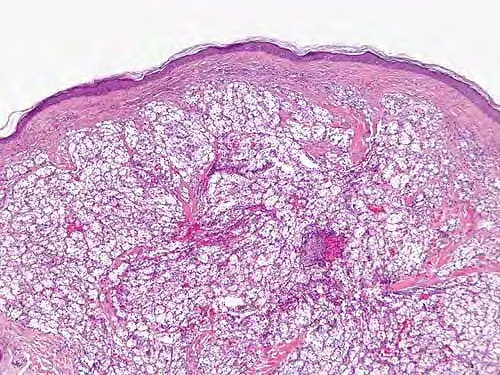

metastasis